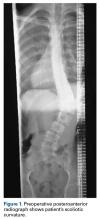

Figure 3.

Preoperative radiographs revealed a 55° right Lenke V C curve (Figures 1, 2). Before the procedure, the patient weighed 111.6 lb and was 175 cm tall. The surgery was uneventful, with a curve correction to about 7° (Figures 3A, 3B). No abnormalities were noted during intraoperative neurologic monitoring. After an unremarkable postoperative course, on postoperative day 19 the patient presented to the emergency department (ED) with abdominal pain, nausea, and vomiting of 3 days’ duration. Right lower quadrant ultrasound revealed nonspecific fluid-filled bowel loops, and the patient was discharged with antiemetics and instructions for hydration.